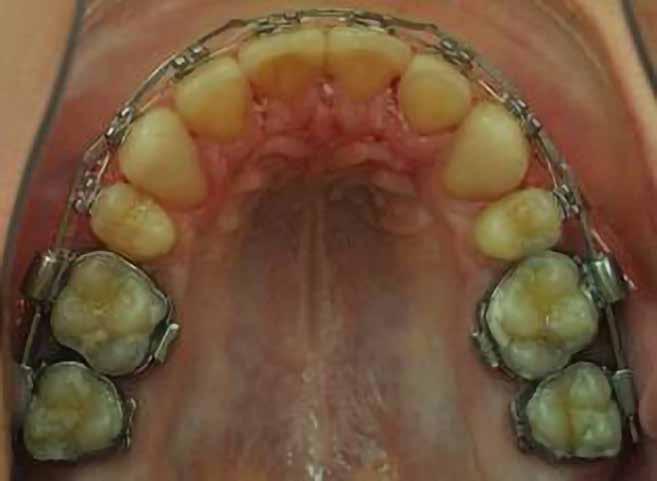

Dr. Ivana Dubovská, dr. Barbora Vágnerová, dr. Wanda Urbanová (Csehország), Dr. Veiszenbacher Éva, dr. Borbély Zoltán, dr. Borbély Péter (Dr. Borbély Fogszabályozási Stúdió, Budapest)

SZEMFOG ÉS KISŐRLŐ FORMÁZÁSA KISMETSZŐ APLÁZIA RÉSZÁRÁSSAL

TÖRTÉNŐ KEZELÉSE SORÁN

Absztrakt

A hiányzó oldalsó kismetszők részárással történő kezelése során a szemfogak és oldalsó fogak meziális mozgatása közben a fogszabályozó orvosnak csiszolással kell a fogak formáját igazítani. Már a kezelés elejétől a szemfog elcsiszolása nem csak az incizális részre kell hogy kiterjedjen, hanem az approximális, palatinális és a vesztibuláris felszín éli negyedére is. Így érhetünk el egy rövidebb klinikai koronát, a vesztibulo-orális méret csökkenését, egy incizális élet, valamint a szemfog megfelelő pozicionálását a kismetsző helyén. A túl széles szemfog megakadályozza a megfelelő interkuszpidáció kialakítását az oldalzónában. A palatinális felszín elcsiszolásával biztosítjuk az interferenciák nélküli metszővezetést, és a megfelelő overjetet a frontfogak enyhe érintkezésével. Ha a szemfogra a későbbiekben esztétikai pótlás készül, a megfelelő approximális elcsiszolás (az esztétikai fogorvossal történő egyeztetés után) biztosítja a zenith kívánatos pozícióját a későbbi felépítéshez. A mezializált kisőrlő palatinális csücskének elcsiszolására csak akkor van szükség, ha ez akadályozza a megfelelő fogérintkezést. Az első kisőrlő mindkét csücske fontos a már a szemfog helyén álló fog esztétikai és funkcionális beállításához.

A szemfog oldalsó kismetsző helyére történő bemozgatása során a fog átalakítása javasolt a két fog eltérő morfológiai adottságai miatt (1. a-b. ábra). A fog kontúrozása, vagy úgynevezett formázása magába foglalja az approximális felszínek elcsiszolását, valamint a többi fogfelszín igazítását a kívánt fogformának megfelelően [1].